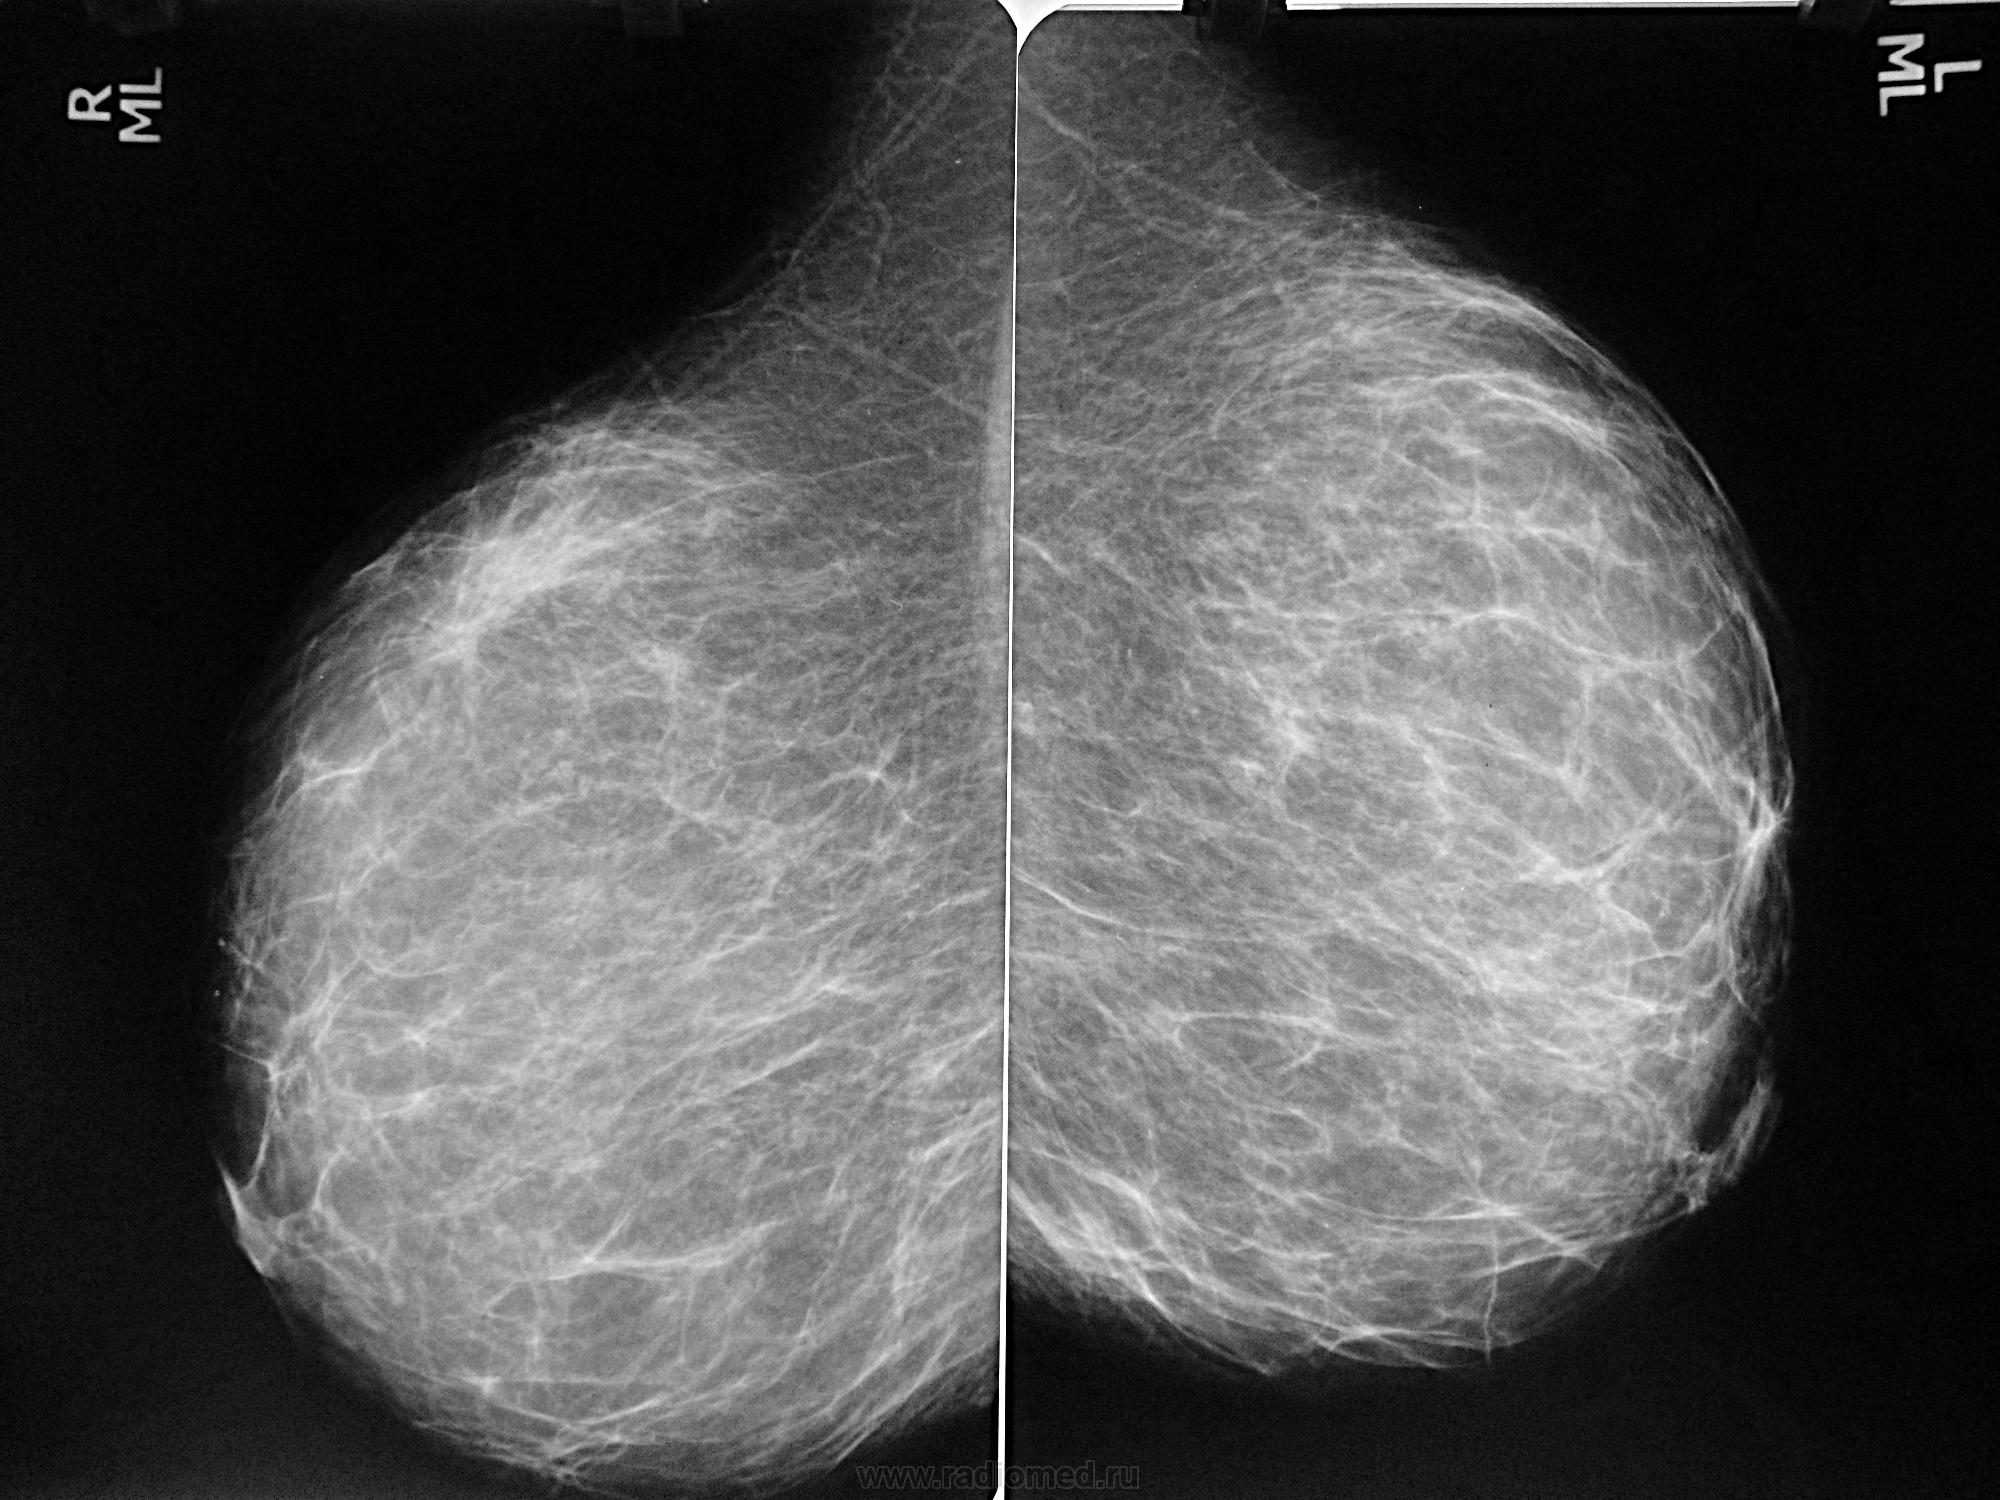

Аномалии молочной железы: медицинские примеры и визуализация

Раздел: Мудрость в деталях